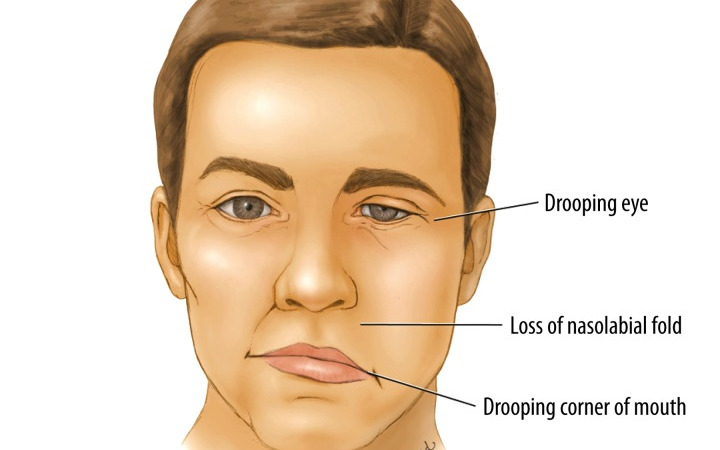

Facial Palsy

The VIIth cranial Nerve has its nucleus in the Pons, and takes a rather winding route before exiting the skull through the stylomastoid foramen. It then passes through the parotid gland, splitting into 5 branches: Temporal, zygomatic, buccal, mandibular and cervical.